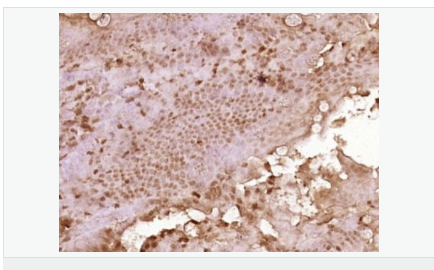

Expressed in enterocytes of small and large intestinal mucosa (at protein level). Expressed in enterocytes, chromaffine and interstitial cells.